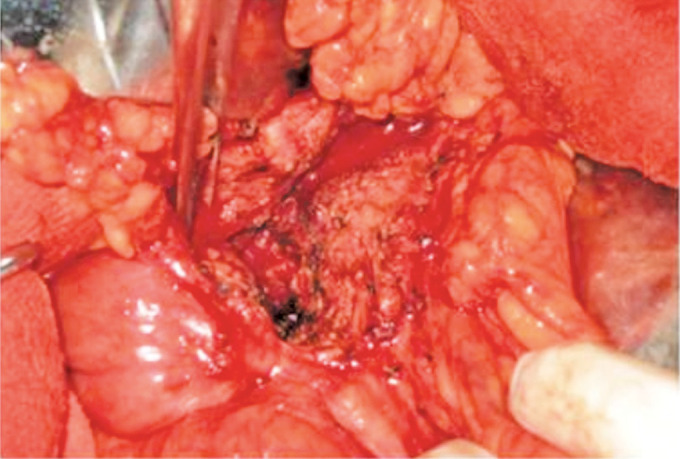

Materials and methods: This is a retrospectively analyzed prospective study conducted at KIMS-Sunshine Hospital, Secunderabad. We evaluated 48 patients who underwent the Frey procedure from 2016 to 2021, each with a follow-up period of at least 1 year. The assessment comprised the validated Izbicki pain score along with evaluations of exocrine and endocrine functions, quality of life using the SF-6 questionnaire, and nutritional status, considering factors such as steatorrhea, glycemic control, and weight gain.

Results: The total number of patients enrolled was 52. Four patients were identified intraoperatively as having malignancy by frozen section and were therefore converted to the Whipple procedure. Therefore, 48 patients (30 = male, 18 = female, mean age 35.2 years) were analyzed in this study. About 6 patients underwent hepaticojejunostomy along with Frey's procedure in view of benign biliary stricture.In this study of 48 patients, the preoperative mean overall pain score was 66.67. Postoperative mean overall pain scores were recorded at 3, 12, 36, and 60 months, showing values of 6.27, 6.37, 8.26, and 8.42, respectively. These results indicate a clear and statistically significant (p < 0.05) reduction in pain both in the immediate and extended follow-up periods.In the first 3 months following surgery, there was weight gain in most of the patients (65%). Though some patients showed mild weight loss subsequently on long-term follow-up, it was not statistically significant (p-value = 0.041).The SF-36 quality of life questionnaire indicated a general improvement in quality of life for the entire group, largely attributable to a reduction in pain. Preoperatively, the mean physical component score (PCS) and mental component score (MCS) were 25.37 ± 6.67 and 26.28 ± 9.94, respectively. These scores increased to 57.78 ± 15.56 and 48.30 ± 26.82 at 3 years, with a p-value of < 0.05.

Conclusion: Frey's procedure is safe and effective in relieving pain in chronic calcific pancreatitis (CCP) with improved quality of life and seems to be better than PD stenting. However, it has no role in the control of exocrine and endocrine pancreatic insufficiency.